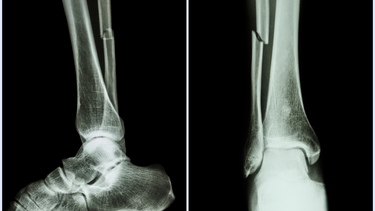

Việc chẩn đoán chính xác cần được xác định bằng X-quang hoặc CT scan tại cơ sở y tế.

Phẫu thuật kết hợp xương

Với các trường hợp gãy phức tạp, gãy hở hoặc di lệch nhiều, cần tiến hành phẫu thuật kết hợp xương bằng đinh nội tủy, nẹp vít hoặc khung cố định ngoài. Mục tiêu là tái lập hình dạng ban đầu và tạo điều kiện cho xương liền đúng vị trí.